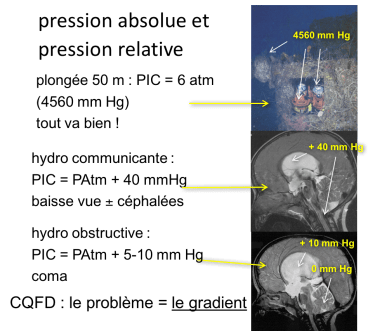

globalement, l’hyperpression est bien tolérée par le système nerveux à condition que tous les compartiments anatomiques soient à la même pression ; s’il existe un gradient de pression, la région sur laquelle ce dernier s’exerce souffre et devient symptomatique, même pour une pression peu élevée (Cf. ci-contre).

le gradient de pression

il s’exerce aux régions d’interface entre :

- intérieur et extérieur : le canal optique d’où oedème papillaire, risque de neuropathie optique et de cécité

- compartiments intracrâniens : engagement temporal, sous-falcoriel

- compartiment intra-crânien et spinal : engagement tonsillaire